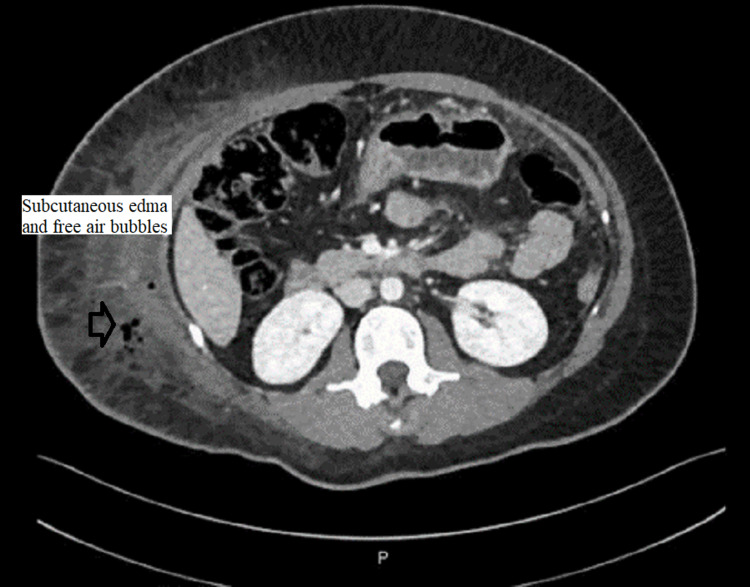

CT abdomen was done and showed a large amount of free fluid in the perihepatic, peri-splenic, and pelvic regions, along with extensive subcutaneous edema and stranding with free air within the right lateral abdominal wall (Figures 3–5). In addition, the CT revealed a mild intrahepatic biliary duct and CBD dilatation.